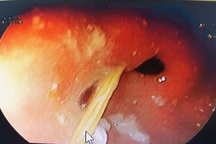

Ekip phẫu thuật do bác sĩ CKII Nguyễn Văn Dũng, Trưởng Khoa Ung bướu 1 đã nhanh chóng mổ cấp cứu. Theo đó, dạ dày mặt trước hang vị có một tổn thương kích thước 1x1cm mủn nát trên nền ổ loét kích thước 4x4 cm. Phẫu thuật viên đã cắt đoạn dạ dày, nối dạ dày và tá tràng, thiết lập lại lưu thông tiêu hóa… để xử trí triệt để tổn thương, đồng thời với việc hồi sức nội khoa tích cực để cứu sống người bệnh.